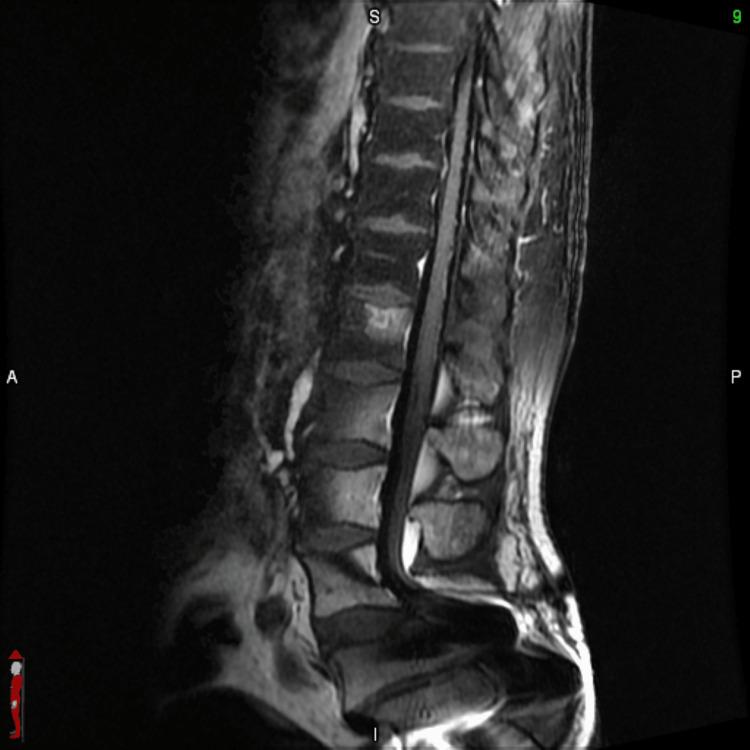

一例非小细胞肺癌所致MRI阴性的柔脑膜疾病病例

A Case of MRI-Negative Leptomeningeal Disease From Non-small Cell Lung Cancer.

Leptomeningeal disease (LMD) is a rare complication of advanced non-small cell lung cancer (NSCLC), associated with a poor prognosis. We report the case of a 55-year-old man, who presented with a metastatic NSCLC with limited brain and abdominal metastases. He was treated with both chemoimmunotherapy and stereotactic radiotherapy (SRT) to the brain. Despite treatment, the patient experienced progressive neurological symptoms not in keeping with the extent of disease seen on imaging of the brain. Due to this incongruence between symptoms and radiologic findings, he underwent a lumbar puncture, which had positive cytology for LMD. He had a rapid progression of symptoms and died six days after the discovery of LMD. We review the available literature regarding the prevalence of MRI-negative LMD from a solid primary malignancy.

摘要

软脑膜疾病(LMD)是晚期非小细胞肺癌(NSCLC)的一种罕见并发症,预后较差。我们报告了一例55岁男性病例,该患者患有转移性NSCLC,脑和腹部转移灶有限。他接受了化疗免疫治疗和脑部立体定向放射治疗(SRT)。尽管进行了治疗,但患者仍出现了与脑部影像学所见疾病范围不符的进行性神经症状。由于症状与放射学检查结果不一致,他接受了腰椎穿刺,脑脊液细胞学检查显示LMD呈阳性。他的症状迅速进展,在发现LMD后六天死亡。我们回顾了有关实体原发性恶性肿瘤中MRI阴性LMD患病率的现有文献。